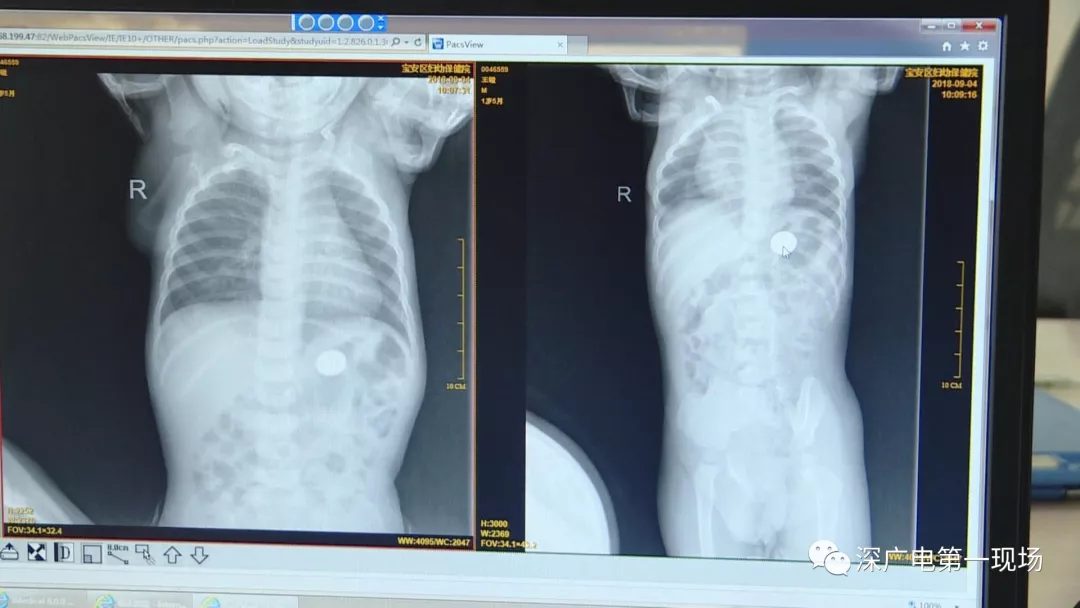

細(xì)心的醫(yī)生竟從

孩子的胸片中有了意外發(fā)現(xiàn)

9月4號(hào),一名1歲零5個(gè)月的男嬰因在家中摔傷,被父母送到了寶安區(qū)婦幼保健院,醫(yī)生診斷為左側(cè)尺橈骨骨折。在進(jìn)行全麻手術(shù)之前,院方例行對(duì)嬰兒進(jìn)行了周身檢查。手術(shù)前,兒外科醫(yī)生趙冠聰在查看患者的胸片時(shí),發(fā)現(xiàn)這名嬰兒的胃部有一枚硬幣大小的暗影。

胃部取出一角硬幣

已吞咽半月之久

經(jīng)過兩個(gè)小時(shí)的時(shí)間,兒科醫(yī)生郭景濤為患兒取出了藏在胃底的一角錢硬幣。目前,患兒已經(jīng)痊愈出院。